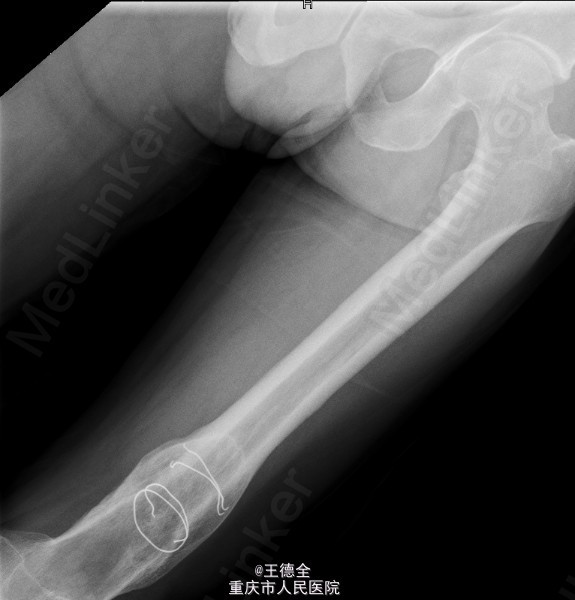

患者男,40岁,因“左股骨下段骨折术后4+年,左膝反复肿痛2年余”入院;自诉于4年前不慎被石块砸伤左大腿,伤后即觉左大腿疼痛,流血,左下肢活动障碍,患者伤后即到当地医院就诊,诊断为:"左股骨下段开放性骨折",予骨折切开复位内固定术,术后3个月下地行走,术后内固定螺钉松动、脱落,近两年来出现左膝关节肿胀、疼痛,活动时肿胀、疼痛症状加重,无畏寒发热、肢端麻木等,患者病后曾到当地医院就诊,予服药治疗后症状无明显好转,为进一步诊治遂来我院就诊,门诊拟"左膝骨性关节炎"收住我科,病程中,患者一般情况尚可,睡眠、饮食可,大小便正常,体重无明显改变。

查体:生命体征平稳,心肺腹未见异常;膝关节周围课件明显肿大,左膝关节活动受限,皮温略高;左股骨下端可扪及肿大,腘窝有一处大小约5x4cm的肿块,辅查x线片如下。